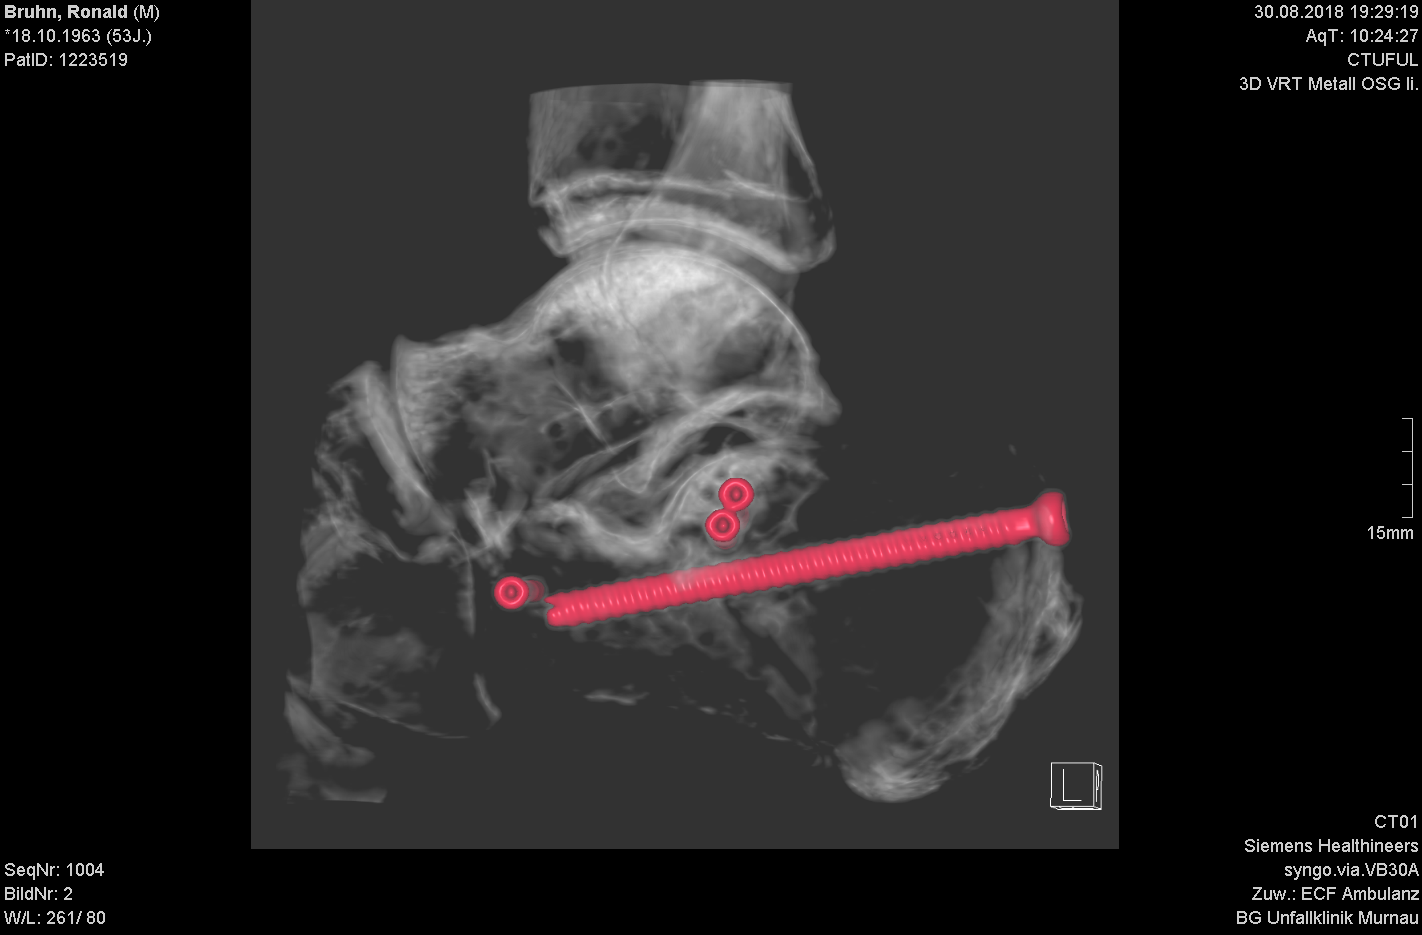

Postoperative Fehlstellungen

Schwere Knochenbrüche stellen eine große Herausforderung für der Operateur wie auch den Betroffnen dar. Heilungsverzögerungen aufgrund schwerer Begleitverletzung der Weichteile (z.B. offene Frakturn) resultieren nicht selten in Fehlstellungen. Diese können die Entwicklung von Arthrose fördern. Sie zu erkennen und ggf auch zu korrigieren erfordern modernste Methoden der OP Planung und Umsetzung wie auch große operative Erfahrung.